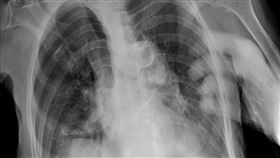

醫揭X光片多1隻手 看護1句全場毛真相曝

北市聯醫陽明院區胸腔內科主治醫師蘇一峰活躍於社交平台...